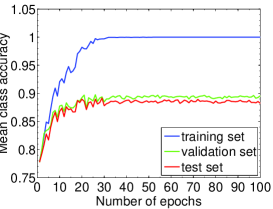

We highlight that training-relevant hyper-parameters can significantly affect the convergence of cost function, the learning speed and the generalization capability of the network. Their impacts are demonstrated via the learning curves of MCA on training, validation and test sets shown from Fig. 4 to Fig. 8. In each figure, we focus on one hyper-parameter while the others are set to their optimal values in Table 2.

Fig. 4 LABEL:sub@subfig:lr1 indicates that when learning rate is small, e.g., , the learning process is so slow that the MCA of the three sets have not become stable in epochs. Properly increasing the learning rate effectively improves learning efficiency and the MCA becomes stable in epochs, as shown in Fig. 4 LABEL:sub@subfig:lr2. At the same time, an over-large learning rate, e.g., , will destabilize the learning process and degrade the classification performance. Also, Fig. 5, 6 and 7 demonstrate the impacts of mini-batch size, momentum and weight decay, respectively.

The comparison in Fig. 8 shows that the dropout strategy (Hinton et al., 2012) shall be used cautiously. When dropout with ratio of (randomly setting the activations to zero with probability of ) is applied to the first fully-connected layer of our CNN system, the learning process becomes slow and fluctuated on ICPR2014 cell dataset. A stabler and faster learning process without overfitting on the test set is gained when removing dropout, as well as better classification performance. This indicates that the neurons at the first fully-connected layer may have to work together to distinguish different staining patterns. In light of this, we decide not to employ dropout when training our network on ICPR2014 dataset.

In sum, among the hyper-parameters of a CNN, the learning rate, mini-batch size, momentum coefficient, and weight decay coefficient can significantly impact the network training process. They have to be carefully tuned before satisfactory classification performance is obtained. For our deep CNN system, with the hyper-parameters set in Table 2, we can achieve the MCA of % on the test set of ICPR2014 dataset without using data augmentation.